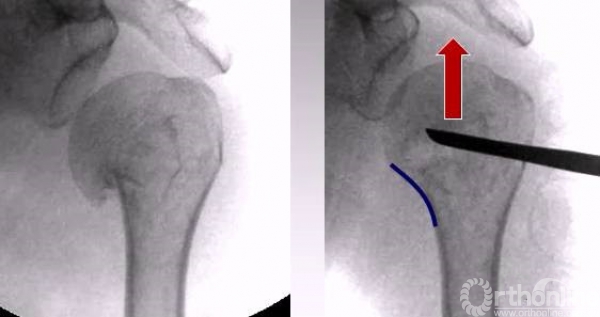

2.用骨拨进行头下翘拨复位。

1.内侧需要完成支撑,复位肱骨距,翘拨要完成正位、侧位、腋位的综合复位。

1.克氏针摇杆技术;

3.骨拨翘拨技术;

正位的翘拨复位

腋位的翘拨复位